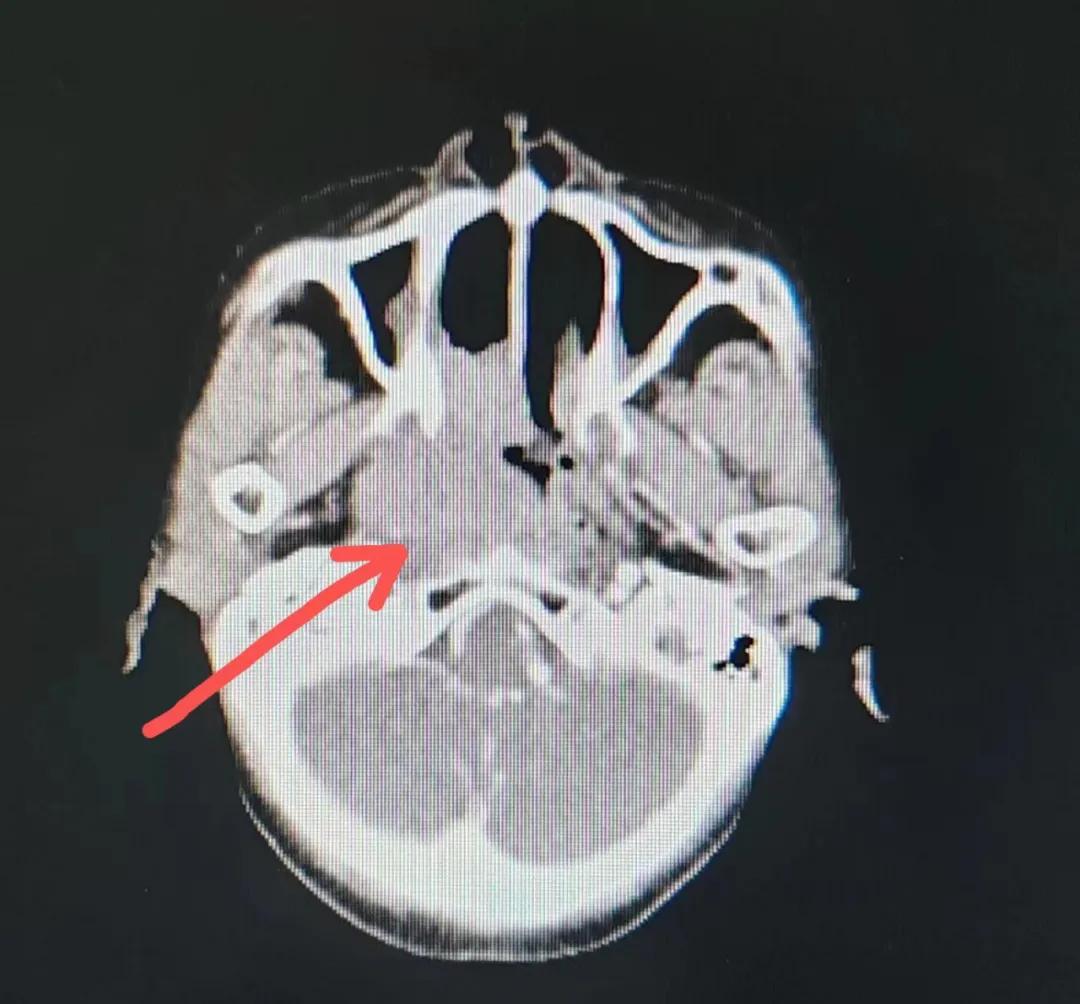

70歲的彭阿姨,5個(gè)月前因鼻部瘙癢伴流血不止在當(dāng)?shù)卦\所治療,瘙癢和出血癥狀不但沒(méi)有得到有效控制,反而進(jìn)行性加重,并出現(xiàn)鼻腔堵塞、進(jìn)食困難,經(jīng)外院病理活檢確診為“鼻腔惡性淋巴瘤”。不斷加重的病痛已嚴(yán)重影響了老人的生活質(zhì)量,為求診治,患者及家屬于今年2月份慕名來(lái)到了市二院放療科。

治療前

老人因鼻部腫物堵塞鼻腔并且侵犯鼻咽導(dǎo)致鼻塞、疼痛、吞咽困難,身心都備受煎熬,趙亮主任在詢問(wèn)其病史期間幾度落淚。趙亮主任向患者及家屬解釋說(shuō):“現(xiàn)代放療比過(guò)去的傳統(tǒng)放療設(shè)備先進(jìn),技術(shù)不斷提升,能對(duì)腫瘤區(qū)域的照射劑量進(jìn)行優(yōu)化,做到準(zhǔn)確定位、精準(zhǔn)照射,同時(shí),最大限度地降低正常組織的受量,對(duì)全身情況影響很小。”

考慮到患者年齡較大、體質(zhì)差,手術(shù)難度大,且常規(guī)的放射治療難以保護(hù)患者晶體造成患者雙眼視力損傷,放療團(tuán)隊(duì)以最快的速度制定了精準(zhǔn)放射治療方案并開(kāi)始為其實(shí)施治療。僅僅數(shù)日后,老人腫塊出血即得到控制,腫塊明顯縮小,放療20次后腫塊迅速縮小!